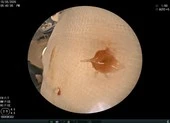

Khi nội soi, các bác sĩ gắp ra được dị vật là một mảnh xương lươn (0,5x0,3cm) gắm sâu vào thành thực quản và gây rách một đoạn khoảng 2cm, phải khâu vá lại. Sau hơn một tháng điều trị, tình trạng trẻ cải thiện dần, cai được máy thở, tỉnh táo, vết thương cạnh cổ, thực quản hết mủ dịch, lành lặn và chuẩn bị được cho ăn qua đường miệng trở lại.